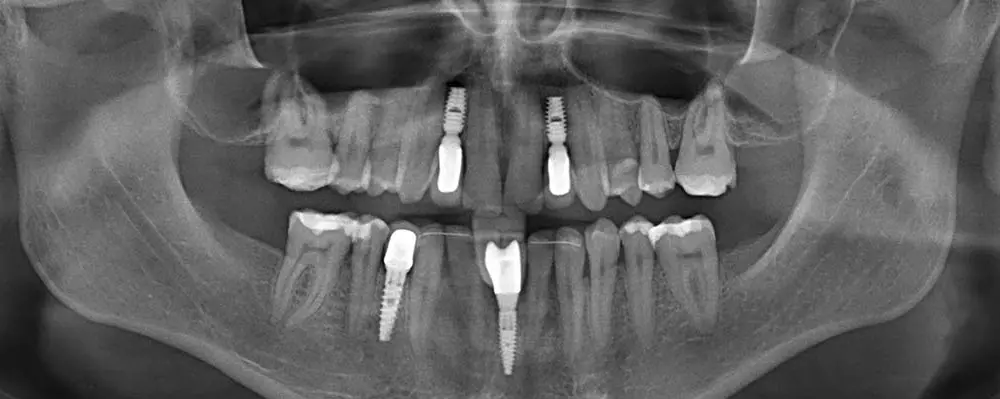

PRODUCT & PRACTISE

- Marcin Aluchna

- 31 stycznia 2020